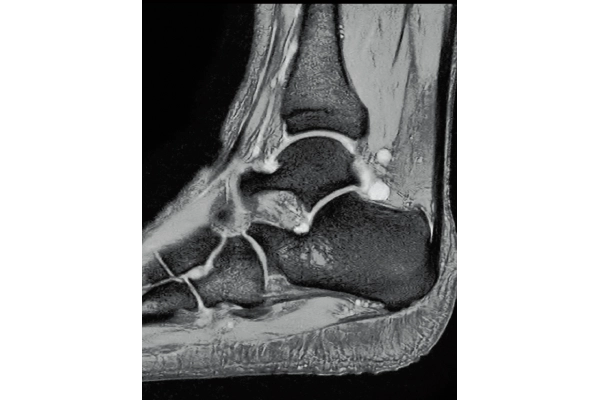

3D Bone

0.93×0.93×1.2(0.6)mm

1.1×1.1×1.2(0.6)mm